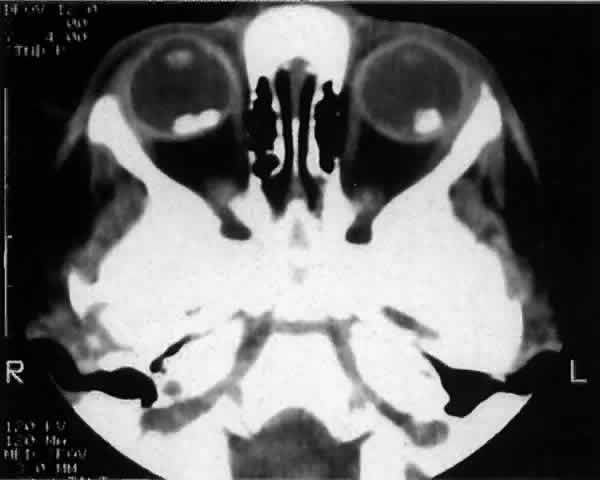

Ocular abnormalities associated with leukocoria15 include retinoblastoma, persistent hyperplastic primary vitreous, Coats' disease, retinopathy of prematurity, cataracts, toxocariasis, chronic retinal detachment, retinal astrocytoma, previous vitreous hemorrhage,73 and endogenous endophthalmitis with calcification.74 Imaging studies to aid in the diagnosis include computed tomography (CT), magnetic resonance imaging (MRI), and B-scan ultrasonography.73,75,76 CT effectively identifies both intraocular calcification and intracranial involvement (Fig. 3). MRI may be more effective in distinguishing Coats' disease, persistent hyperplastic primary vitreous, and toxocariasis from retinoblastoma.73 Calcification may be seen with Coats' disease77 or in rare cases may be absent with retinoblastoma.78

Fig. 3. Computed tomographic scan of a bilateral calcified retinoblastoma.